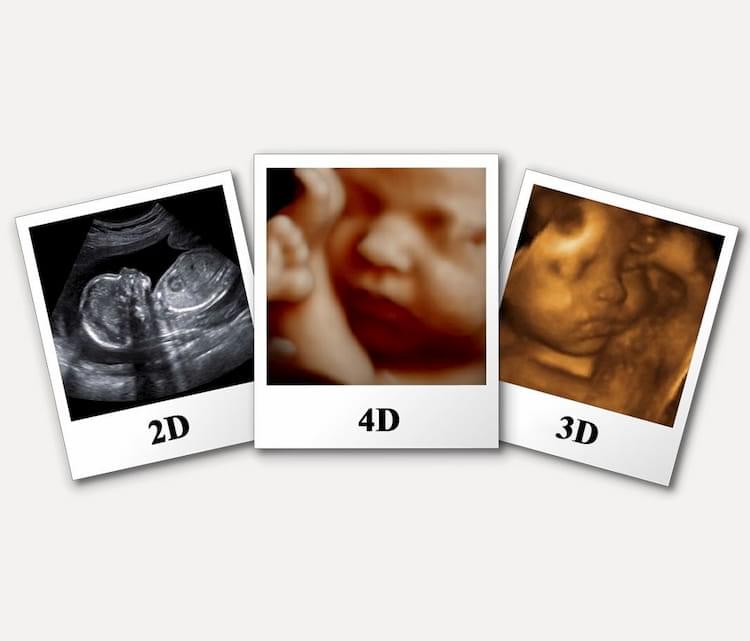

С медицинской точки зрения этот тест редко необходим. Но увидеть черты лица будущего ребенка до того, как он родился – это приятные впечатления для будущей мамы. Поэтому родители обычно сами «назначают» это обследование.

В хороших клиниках объемные ультразвуковые исследования проводят много лет, современные аппараты даже снимают видео в отличном качестве.